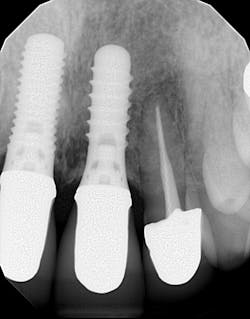

Radiographic assessment revealed implant-supported crowns on teeth nos. 8 and 9 (figure 1). Clinically, no. 9 was mobile in all directions, but no. 8 also had a slight buccolingual rock to it.